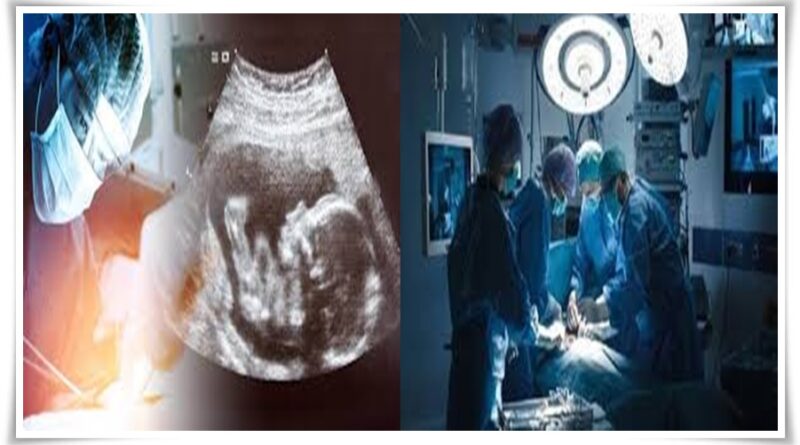

గర్భంలోని శిశువుకు హార్ట్ ఆపరేషన్

ప్రపంచంలోనే భారతీయ వైద్యులు గొప్ప ఘనత సాధించారు. ప్రపంచంలో మొట్ట మొదటిసారిగా గర్భస్థ శిశువుకు విజయవంతంగా హార్ట్ ఆపరేషన్ చేసి రికార్డు సాధించారు రెయిన్ బో ఆసుపత్రి వైద్యులు. 27 వారాల గర్భస్థ పిండానికి అయోర్టిక్ స్టెనోసిస్ అనే సమస్యను గుర్తించిన రెయిన్ బో ఆస్పత్రి చీఫ్ పీడియాట్రిక్ కార్డియాలజిస్ట్ డాక్టర్ నాగేశ్వర రావు కోనేటి అరుదైన శస్త్రచికిత్స చేసి, ప్రాణం పోశారు. గతంలో ఇలాంటి సమస్యలు గుర్తిస్తే గర్భవిచ్ఛిత్తి మాత్రమే మార్గంగా ఉండేది. ఒకవేళ సమస్య ఆలస్యంగా గుర్తిస్తే బిడ్డ పుట్టిన కొన్ని రోజులకే కన్నుమూసేది. ఇలాంటి పరిస్థితి రాకుండా వైద్య, శాస్త్ర సాంకేతిక రంగాల అభివృద్ధి తల్లులకు కడుపు కోత తగ్గిస్తోంది.